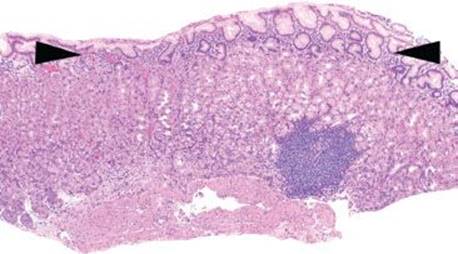

AMAG characteristically shows body/fundus-predominant injury and demonstrates a combination of the following morphologic features (Figs. 2.85–2.89).

• Basal Lymphocytic Infiltrate of Oxyntic Mucosa

• Atrophy of Oxyntic Mucosa (Patchy or Complete)

• Intestinal and Pyloric Metaplasia of Oxyntic Mucosa

• Lymphoid Aggregates in Oxyntic Mucosa

BASAL LYMPHOCYTIC INFILTRATE SUBPATTERN

This subpattern of chronic gastritis is defined by a low-lying lymphocytic infiltrate that expands the lamina propria between the base of the gastric glands and the muscularis mucosae. The prototypical case shows a “band-like” infiltrate hugging the muscularis mucosae at scanning magnification. High-power examination shows admixed plasma cells and occasional eosinophils, but the dominant cell type is lymphocytes (Figs. 2.79, 2.97 and 2.98).